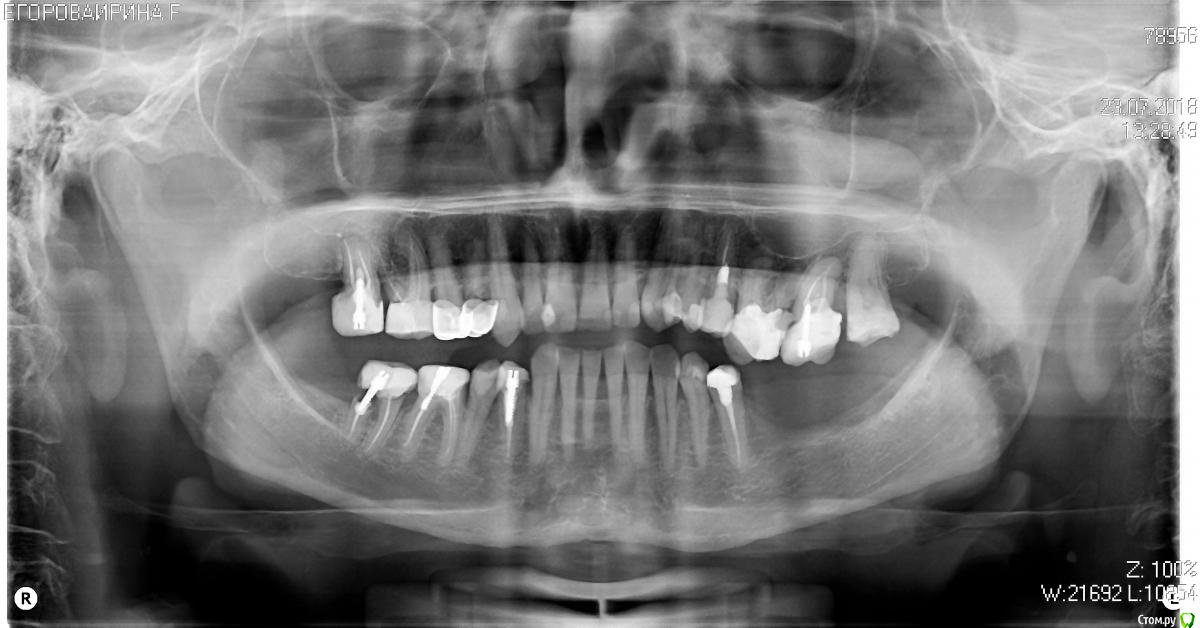

У меня следующая  БОЛЬШАЯ проблема: в нижней левой челюсти из-за отсутствия 3-х зубов произошло истончение десны. По этой причине произошла деформация верхней челюсти.

Врач-ортопед рекомендовал наращивание костной ткани с последующей установкой 3-х имплантов, или протезы.

Панорамный снимок прилагаю.

У вас там достаточно сложный случай по наращиванию костной ткани. Абы кто такое не сделает. Во всей Москве может 10-15 врачей только смогут.